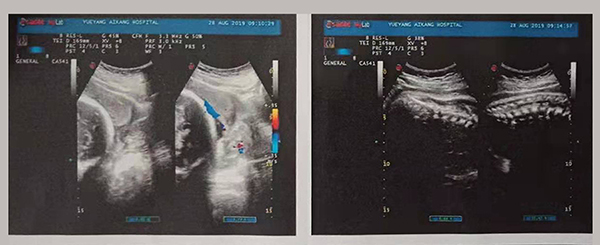

干得漂亮!岳陽愛康醫(yī)院成功搶救一名完全性前置胎盤產(chǎn)婦!

近日,岳陽愛康醫(yī)院產(chǎn)科團(tuán)隊(duì)成功搶救了一名完全性前置胎盤的產(chǎn)婦。完全性前置胎盤是妊娠期的嚴(yán)重并發(fā)癥,是分娩期子宮切除的一個(gè)重大高危因素之一,是引起孕產(chǎn)婦死亡和圍生兒死亡的重要原因之一。

2019年8月24日,易女士出現(xiàn)陰道流血,在岳陽縣人民醫(yī)院住院,住院期間予以安治、止血,于26日出院。28日早晨6點(diǎn)再次出現(xiàn)陰道流血,量多、顏色鮮紅、三片衛(wèi)生巾均浸透,遂來岳陽愛康醫(yī)院產(chǎn)科。

易女士一進(jìn)入病房就引起了岳陽愛康醫(yī)院產(chǎn)科主任高君萍的高度重視,考慮到手術(shù)的風(fēng)險(xiǎn)大,手術(shù)過程復(fù)雜,有可能出現(xiàn)新生兒窒息、產(chǎn)婦大出血等危及母嬰生命的并發(fā)癥,甚至切除子宮可能。在檢驗(yàn)科充分術(shù)前配血、血漿的準(zhǔn)備及全院MDT(多學(xué)科聯(lián)合會(huì)診),立即進(jìn)行手術(shù)。

術(shù)中,擺在產(chǎn)科團(tuán)隊(duì)面前的第一個(gè)嚴(yán)峻考驗(yàn)出現(xiàn)了,整個(gè)子宮下段前壁膨隆血管怒張!迅速設(shè)計(jì)子宮切口,取出胎兒,面臨又一嚴(yán)峻的考驗(yàn),胎盤大面積植入整個(gè)子宮下段前后壁,迅速行雙側(cè)子宮動(dòng)脈下行支結(jié)扎,迅速人工剝離胎盤以及卵圓鉗鉗夾剩余胎盤組織,植入的胎盤處理干凈后子宮下段前后壁多處肌層缺損伴有大量活動(dòng)性出血,迅速行子宮下段整形修復(fù)縫合止血……不得不說產(chǎn)婦是幸運(yùn)的,婦產(chǎn)科、手術(shù)麻醉科等多科通力合作,經(jīng)過約2小時(shí)的手術(shù)及搶救止血,術(shù)中共計(jì)出血1500ml,輸懸浮紅細(xì)胞4個(gè)單位,終于保得母女平安,并完美的保留了子宮。易女士術(shù)后恢復(fù)良好,對(duì)婦產(chǎn)科的精湛技術(shù)贊不絕口!